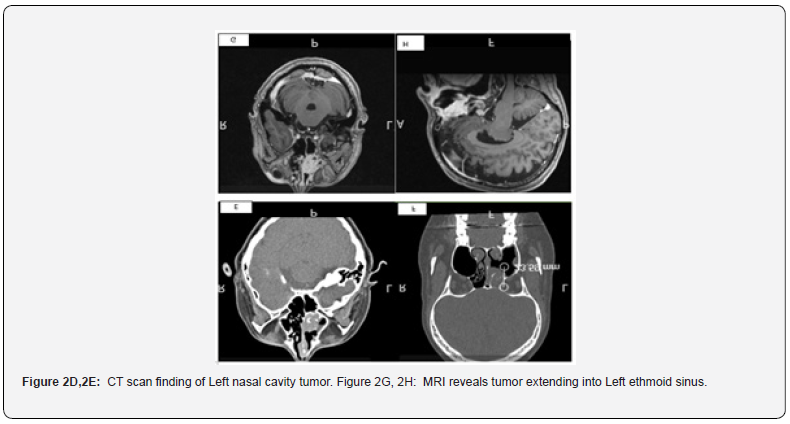

We reported an unusual case of a woman with a sinonasal tumor that mimicked, histologically, metastatic RCC. A-49-year-old women with no significant past medical history presented with 2 months history of headache and recurrent epistaxis for 2 months. She visited ER and 4.5x 4x 2cm high attenuation lesion in the left nasal cavity which is extending into the left ethmoid sinuses and bulging towards the left maxillary sinus on CT scan. The lesion raises the suspicion of polyp or hematoma, and she received treatment with nasal packing. MRI finding revealed 3.0 x 2.6 x 1.5 cm heterogeneously enhancing mass centered in the left middle turbinate and left nasal cavity, internally convoluted cerebriform pattern of enhancement. The mass obstructed the left osteomeatal unit, frontoethmoidal and sphenoethmoidal recesses and associated with mucosal thickening throughout the paranasal sinuses except right sphenoid sinus. She denies any urinary symptoms such as hematuria, abdominal pain and renal masses [3]. Negative lymphadenopathy on physical examination and MRI. CT abdomen finding discovered no suspicious masses in the kidneys or elsewhere in the abdomen or pelvis or suspicious lymphadenopathy. Biopsy of the lesion was taken, and histological findings disclosed carcinoma with clear cell features involving sinonasal submucosa, diffusely infiltrating between the seromucinous glands, and associated with rich vascular network. The tumor cells show nests to sheets of polygonal cells bearing clear to slightly eosinophilic cytoplasm and vesicular nuclei with prominent nucleoli. Extensive immunohistochemical work up showed positivity with CAIX, AE1/AE3, patchy positivity with CK7 and inhibin. The tumor cells are immunonegative for S100, HMB45, PAX-8, P63, CD68, CD163, chromogranin, synaptophysin, SMA, D2-40, ERG, beta-catenin [4]. The proliferation index is low and 10%. Mucicarmine stain is negative. Our diagnosis is clear cell carcinoma favor low-grade sinonasal renal cell like adenocarcinoma(SNRCLA). The case had been sent out for second opinion and outside Pathology agreed with our diagnosis. Wide excision with negative margins has been performed and postoperative recovery was uneventful. 2 months follow-up after wide excision is no recurrence of tumor.

Salivary clear cell carcinoma SCCC is uncommon salivary gland tumor and slightly female preponderant (female to male ratio 1.6:1). SCCC usually occurs in the sixth or seventh decade of life, the palate and base of tongue being the most common primary sites of tumor [5]. Sinonasal location is very unusual location and assumed developed from minor salivary glands in locations. Sinonasal renal cell like carcinoma SNRCLA is a rare, low-grade neoplasm that bears no resemblance to any other sinonasal primary tumor. The tumor also has a female predominance of 2:1. The nasal cavity is the most common site of involvement, followed by paranasal sinuses and nasopharynx. Histologically, the tumor cells have monomorphous cuboidal to columnar glycogen-rich clear cells lacking mucin production [6]. The cellular cytoplasm may be “crystal clear” or may be slightly eosinophilic arranged in follicular/glandular structures to entirely solid and nonglandular, glandular pattern being most dominating in reported cases (Figure 1A,1B,1C,1D). Maharaj et al reported a case of SNRCLA arising from patient with Von Hippel Lindau syndrome and tumor cells are arranged in follicular pattern with focal colloid like secretions. One reported case of SNRCLA was evident for prominent foci of oncocytoid and basophilic tumor cells. SNRCLA has no necrosis with limited pleomorphism and scarce mitotic activity. Hyalinized stroma and evidence of myoepithelial differentiation are not features of SNRCLA. In SCCC, the tumor cells are arranged in nests, cords, and trabeculae. Amyloid like hyalinization can variably accompany SCCC. Our reported case has clear cytoplasmic tumor cells arranged in nests to diffuse sheets [7-10]. The epithelial markers including CK7, CK19, CK14, CAM5.2, and EMA are positive in SCCC and usually express p63, p40 and CK5/6.1 In SNRCLA, most of the reported cases have been positive for CKs7 variable expression of vimentin and S100. Iv Robust cytoplasmic and membranous CA-IX expression was seen in 6 out of 7 SNRCLAs. All SNRCLAs examined for Human melanoma black-45 (HMB45), Melan A, and smooth muscle action (SMA) are negative, thus excluding balloon cell variant of melanoma and PEComa, respectively. As our case described strong immunoreactivity with CAIX, AE1/AE3 and patchy positivity with CK7 and inhibin while negative for HMB45 and S100, the diagnosis is leaning towards the SNRCLA rather than SCCC. In addition, PAX-8 non-immunoexpression and negative imaging findings of abdominal masses and normal renal imaging entirely argue against the possibility of metastatic clear cell renal cell carcinoma (Figure 2D,2E,2G,2H).